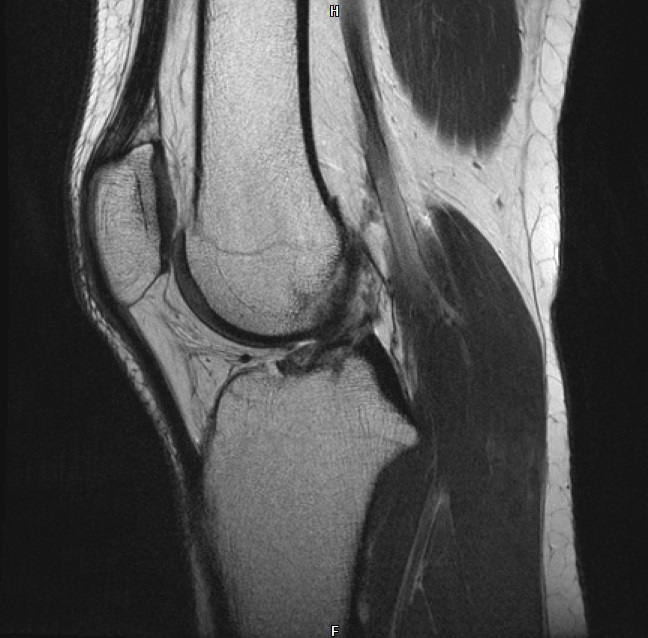

Ich war gerade im MRT wegen Problemen mit meinem rechten Knie. Hab jetzt kurz mal einen auf Dr. Google gemacht und Bilder der häufigsten Verletzungen verglichen mit meinen Bildern. Da bin ich beim vorderen Kreuzbandriss etwas aufmerkasm geworden. Das sind meine Bilder

auf dem letzten Bild sieht man mein hinteres Kreuzband ja wunderbar, es ist ja dieser dunkle "Haken", der Oberschenkel und Schienbein miteinander verbindet.

Nun aber auf dem 3. Bild sollte man doch dasselbe fürs vordere sehen? Aber ich sehe da nur die Ansätze am Schienbein?